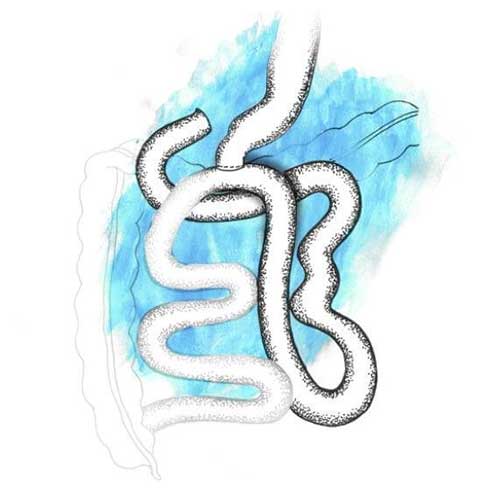

One of the most popular bariatric surgeries across the globe, the laparoscopic sleeve gastrectomy is an irreversible procedure that curtails the size of the stomach by surgically removing approximately two-thirds of it, making it roughly the size and shape of a banana. The procedure also eliminates most of the cells that produce ghrelin, the hunger-inducing hormone; thus, reducing your eating capacity post surgery and helping you lose weight quickly.

This procedure is the preferred choice for younger patients suffering from morbid obesity. It is helpful for patients suffering from various side-effects of obesity, such as diabetes, high blood pressure, sleep apnea, and PCOS. While the laparoscopic sleeve gastrectomy is a great first- stage procedure for patients falling under the super super obese (BMI more than 60-70) category, it is not recommended for patients suffering from severe gastroesophageal reflux disease or large hiatus hernia

Nearly 60 to 80 per cent of your excess body weight will reduce over a period of one-and-a-half years. You will observe rapid weight loss within the first three to four months post surgery, after which the rate of weight loss will slow down. You may also regain the lost weight due to overconsumption of high-calorie foods and liquids, and lack of regular physical exercise. However, you can avoid this, if you follow our exercise, nutrition and lifestyle tips, and maintain a proper follow-up routine.

The nerves of the stomach and the outlet valve (pylorus) are not altered, preserving the function of the stomach. The rest of the gastrointestinal tract anatomy is also not altered, so the food ingested follows the normal course. This results in a lesser chance of vitamin and mineral deficiencies and decreases the possibility of dumping syndrome.

This procedure is the preferred choice for younger patients suffering from morbid obesity. It is helpful for patients suffering from various side-effects of obesity, such as diabetes, high blood pressure, sleep apnea, and PCOS. While the laparoscopic sleeve gastrectomy is a great first- stage procedure for patients falling under the super super obese (BMI more than 60-70) category, it is not recommended for patients suffering from severe gastroesophageal reflux disease or large hiatus hernia.

Nearly 60 to 80 per cent of your excess body weight will reduce over a period of one-and-a-half years. You will observe rapid weight loss within the first three to four months post surgery, after which the rate of weight loss will slow down. You may also regain the lost weight due to overconsumption of high-calorie foods and liquids, and lack of regular physical exercise. However, you can avoid this, if you follow our exercise, nutrition and lifestyle tips, and maintain a proper follow-up routine.

The nerves of the stomach and the outlet valve (pylorus) are not altered, preserving the function of the stomach. The rest of the gastrointestinal tract anatomy is also not altered, so the food ingested follows the normal course. This results in a lesser chance of vitamin and mineral deficiencies and decreases the possibility of dumping syndrome.